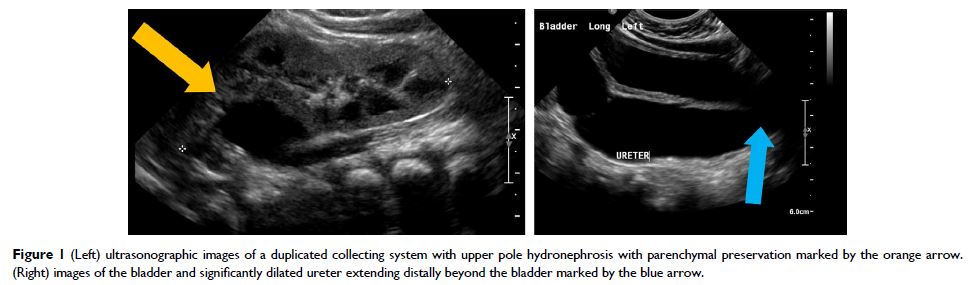

Review

- 作者:Jonathan S Ellison, Thomas S Lendvay

- 期刊:Robotic Surgery: Research and Reviews